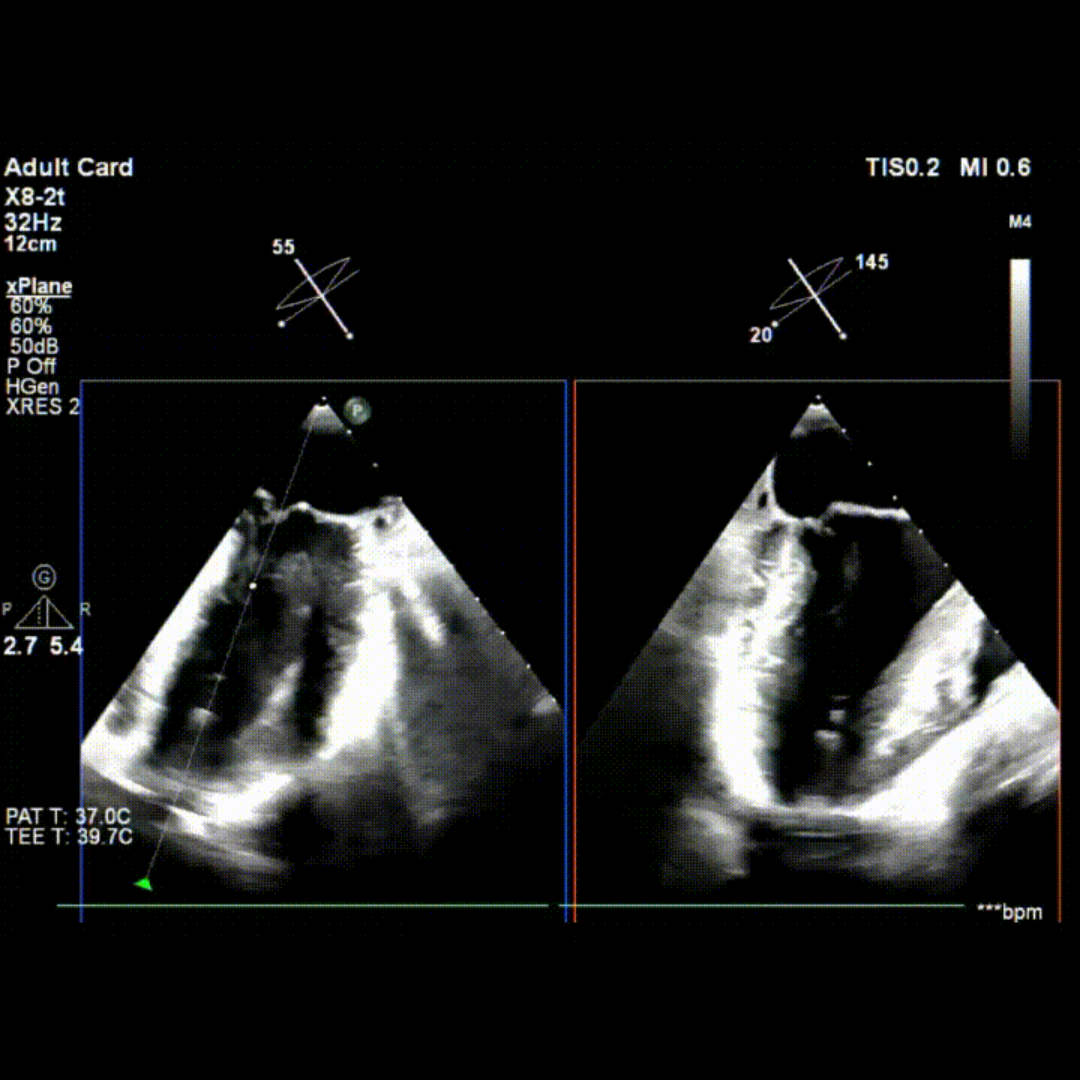

术前TEE影像

术中TEE影像